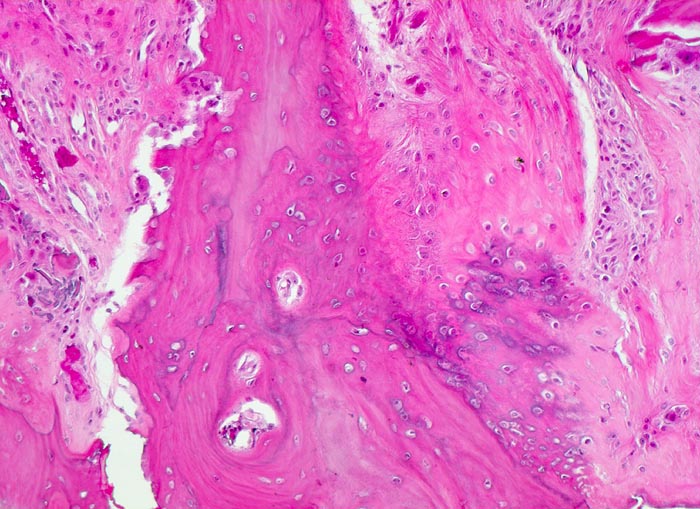

• Ortsständiger Lamellenknochen wird als Leitschiene zur Fasernknochenneubildung benutzt.

• Pseudozystische Hohlräume in den nekrotischen Markräumen.

• Fibrosiertes Mark mit einzelnen thrombosierten Arterien.